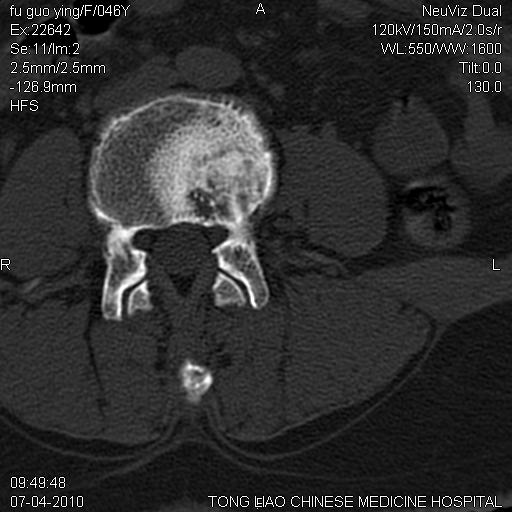

标题: CT27489:患者腰疼,其余椎体未见异常! [打印本页]

标题: CT27489:患者腰疼,其余椎体未见异常!

女性46岁,左髂骨溶骨性破坏+软组织肿块,考虑转移瘤,腰椎为退变/增生硬化/软骨下骨囊变。

髂骨考虑转移瘤 椎体病变不像转移瘤